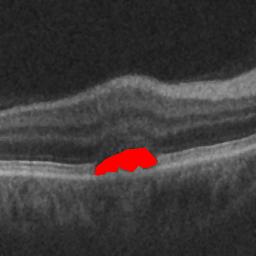

The qualitative results of the proposed system is shown in the Fig. 3. The detection task is evaluated using Area Under the Curve(AUC) metric and the segmentation task is evaluated using Dice Coefficient(DC) metric and the results are presented in Table1

| (a) De-noised OCT slice | (b)Predicted fluid region | (c)Manual fluid segmentation |

| (d) De-noised OCT slice | (e)Predicted fluid region | (f)Manual fluid segmentation |

| (g) De-noised OCT slice | (h)Predicted fluid region | (i)Manual fluid segmentation |

| (j) De-noised OCT slice | (k)Predicted fluid region | (l)Manual fluid segmentation |

| (m) De-noised OCT slice | (n)Predicted fluid region | (o)Manual fluid segmentation |